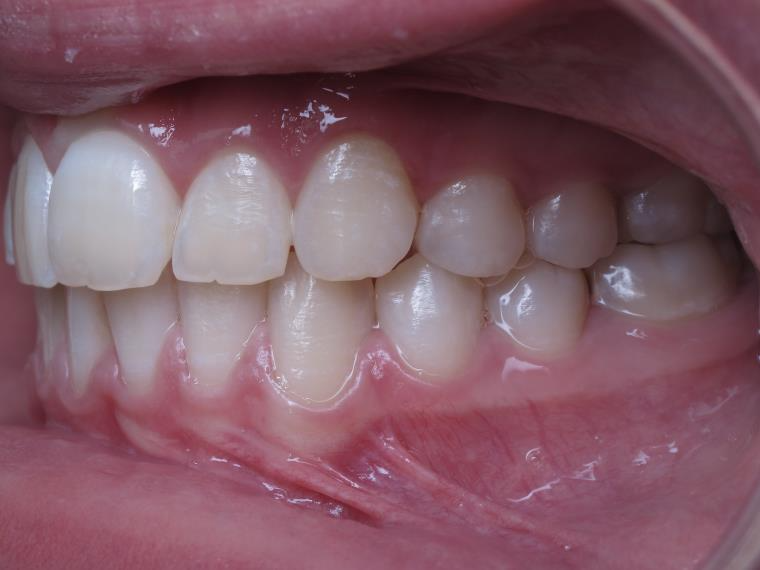

surveillance évolution de la dentition pendant 4 ans

surveillance de la dentition par gouttieres nocturne

bilan début et fin de traitement